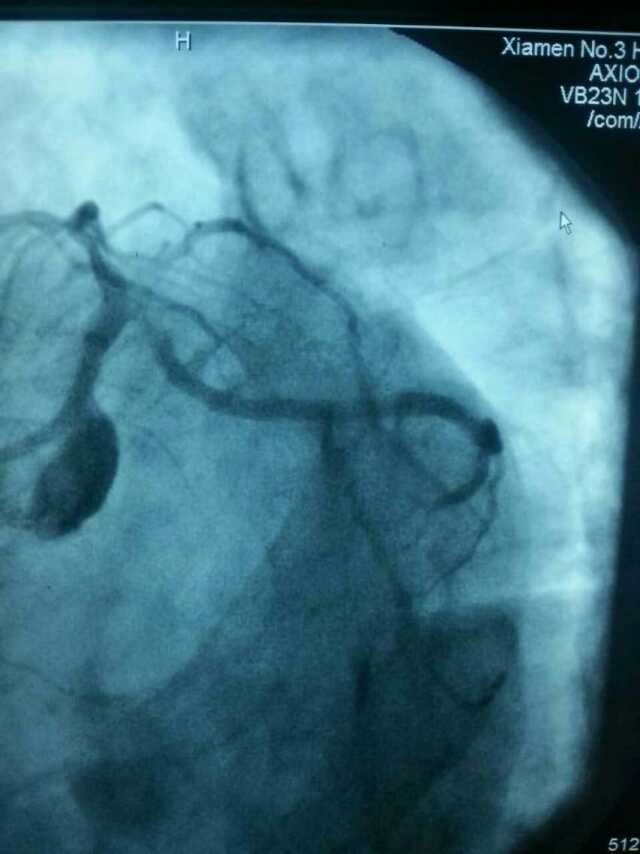

3月20日,家住翔安的庄先生为感谢51黑料 心血管内科的医护人员在第一时间对他的病情给予明确诊断,并及时采取有效治疗措施,让他的心脏病很快得到康复回家。特地送来一面写着“德医双馨,妙手回春”锦旗以表达他们满满的感激之情。